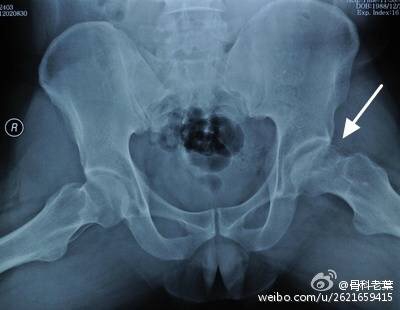

II期 病人有髋部症状,磁共振出现异常,X线片显示股骨头出现透光和硬化改变

III期 磁共振出现异常,X线片显示软骨下塌陷(新月征),股骨头内出现空洞,股骨头没有变扁

II期和III期的患者治疗方法相同,因为此时股骨头虽然还没有变形,暂时还不需要行人工关节置换术,但是股骨头已经出现空洞,随时股骨头就会塌陷变形,所以单纯的股骨头减压术是不能达到治疗效果的。这时就需要在股骨头减压的同时,植入一根支撑棒,顶住股骨头空洞区,防止股骨头在负重的情况下过早塌陷。其他治疗同之前相同,口服以上药物,定期复查,密切观察病情发展,尽量避免重体力劳动和爬山爬楼。

另附典型病例若干: